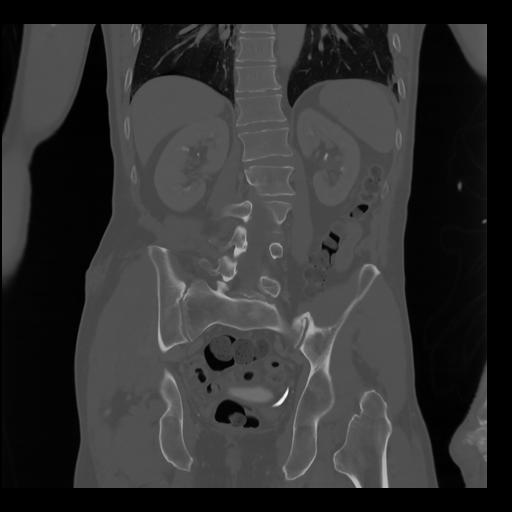

35 CUERPO,CE,Coronal,3.000,CUERPO,Coronal,